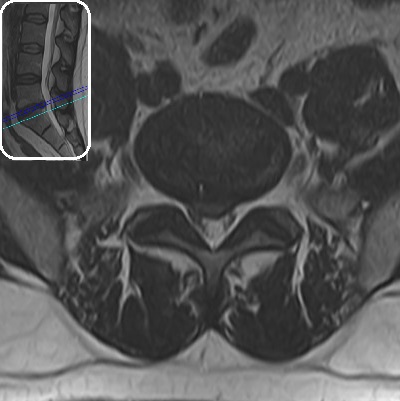

Lomber MRG

incelemesinde L5-S1 seviyesinde santral bir bulging görülmektedir. Sağ

S1 köküne dokunacak şekilde anulus fibrozusta küçük bir açıklık

ve ufak bir ekstrüde fragman varlığından şüphe edilebilse bile, kesin

söylenemez. Aynı seviyede disk içi hipointens ve komşu L5 vertebrası

alt endplate'i ön kısmında dejeneratif sinyal değişikliği görülmektedir

(dejeneratif disk hastalığı). Lomber lordoz korunmuştur. Diğer

disk seviyeleri, faset eklemler ve paravertebral kaslarda belirgin bir

sorun saptanmamıştır.